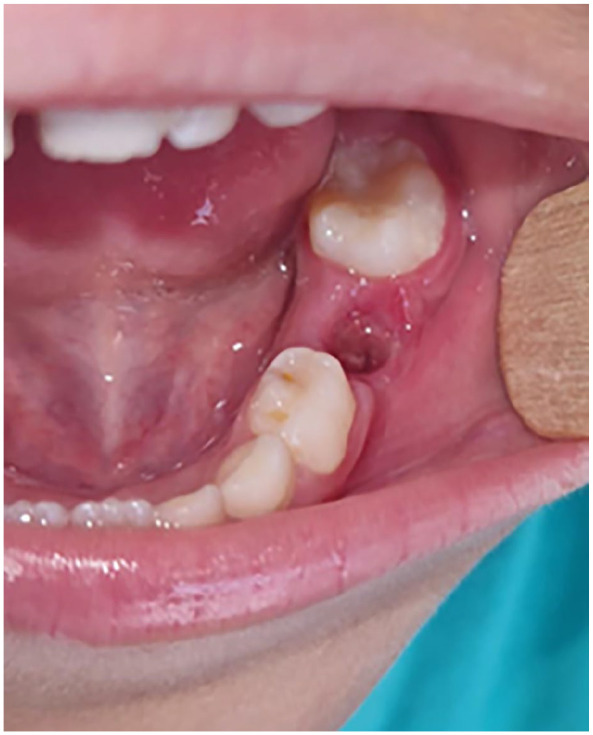

Dentigerous cysts are the most common type of developmental odontogenic cysts. Multiple devices has been described for decompression. The current case report describes the use of a custom-made decompression appliance, designed through a digital workflow, in managing dentigerous cysts. A 7-year-old male patient with no prior medical history was referred to our oral surgery department due to swelling on the left side of the lower jaw. Upon intraoral examination and cone-beam computed tomography (CBCT), a provisional diagnosis of an inflammatory dentigerous cyst related to the impacted premolar was made. A digital decompression appliance was planned using EXOCAD (Exocad Gmbh, Darmstadt, Germany), and produced using a stereolithography (SLA) 3D printer. The appliance were delivered on the day of the cystostomy after extraction of the deciduous molar (tooth 85). In this report, the advancements in digital design technologies were explored enabling the creation of customized cyst decompression devices. Various stages of the design process were discussed, including 3D modeling, material selection, and the integration of digital workflows in the fabrication process. Additionally, the benefits of using such devices were addressed, including improved patient outcomes, enhanced precision in treatment, and the reduction of surgical complications.